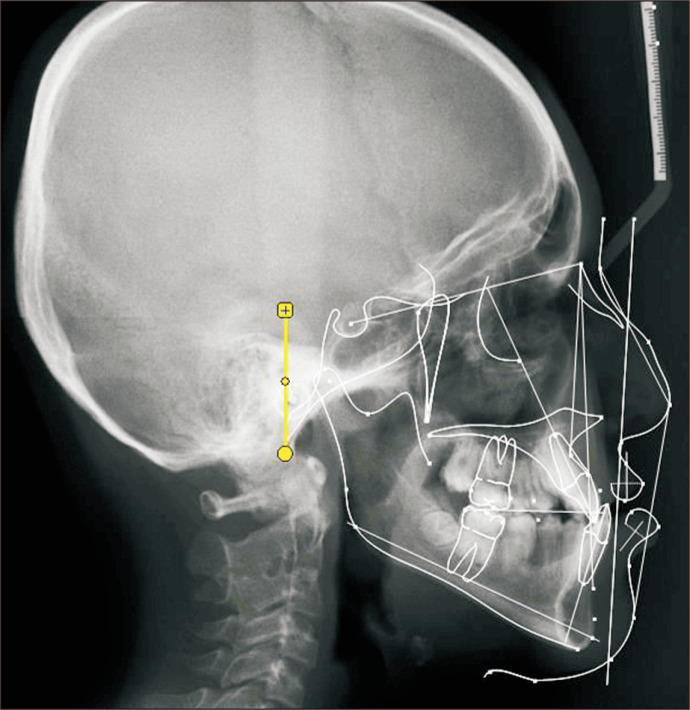

Objectives: Skeletal class III malocclusion presents either with maxillary retrognathism, mandibular excess, or a combination. Dentoalveolar compensations occur with maxillary incisor proclination and mandibular incisor retroclination. The aim of this study is to quantify the amount of incisal compensation in class III skeletal malocclusion and correlate it to the severity of the skeletal base.

Materials and methods: Eleven angular and 7 linear cephalometric measurements were digitized from 57 patients. Axial inclination of the upper and lower incisors was evaluated for compensation. Pearson's correlation coefficient was used to determine the dentoalveolar parameter among those measuring upper and lower incisor position and inclination that correlated most highly with the severity of class III. Linear regression analysis was used to identify the quantum of the incisal compensation.

Results: Upper incisors were proclined and placed anteriorly. However, correlation analysis suggested a less responsive incisor with progressive change in skeletal base. Lower incisors began to compensate only as the severity of class III increased. For every degree of reduction of ANB angle from normal, the incisor mandibular plane angle (IMPA) and L1-GoMe decreased by 0.79° and the L1-GoGn decreased by 0.81°.

Conclusion: The upper incisors contributed more to compensation compared to the lower incisors in a class III skeletal base. As class III severity increased, the upper incisor compensation decreased while that of lower incisors increased. For every degree of reduction in ANB angle, the IMPA and L1-GoMe decreased by 0.79° and the L1-GoGn decreased by 0.81°.